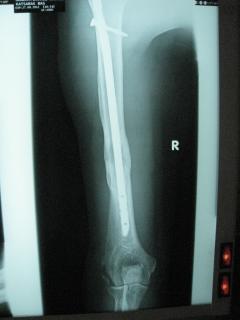

Κατάγματα μακρών οστών άνω και κάτω άκρου

Τα εν λόγω κατάγματα είναι αρκετά συνηθισμένα και συχνά συμβαίνουν μετά από τροχαία ατυχήματα ή πτώση από ύψος. Παρατηρείται εξαιρετικά μεγάλη ποικιλία στη μορφή τους, κατα κανόνα όμως είναι σοβαρά και πολλές φορές ανοικτά – δηλ με τραύμα στο σημείο του κατάγματος – κάτι που αυξάνει τον κίνδυνο λοίμωξης και επιβαρύνει την πορεία της θεραπείας. Στα κατάγματα των άνω άκρων ενδέχεται να υπάρξει και τραυματισμός νεύρων, που χρειάζεται επίσης αντιμετώπιση.

Με τα σύγχρονα μέσα που διαθέτουμε, όλα σχεδόν αυτά τα κατάγματα πρέπει να αντιμετωπίζονται χειρουργικώς. Υπάρχει πληθώρα υλικών οστεοσύνθεσης (πλάκες διαφόρων τύπων, ενδομυελικοί ήλοι, συστήματα εξωτερικής οστεοσύνθεσης) που είναι διαθέσιμα και επαφίεται στην εμπειρία του χειρουργού η επιλογή.

Οπως και άλλοι εξοικειωμένοι χειρουργοί διεθνώς, χρησιμοποιώ τεχνικές ελάχιστης παρέμβασης (Minimal Invasive Surgery), δηλαδή μικρές τομές, επειδή έτσι το χειρουργικό τραύμα είναι ελάχιστο, με αποτέλεσμα ταχύτερη επούλωση. Ταχύτερη πώρωση των καταγμάτων, ταχύτερη κινητοποίηση.

Περίπτωση 2ου ασθενούς